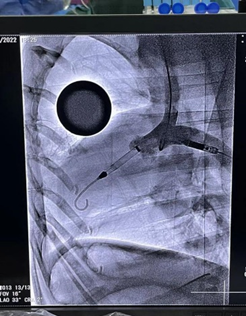

其自主研发的D-OmniHeart已于2022年8月完成全国首例植入,成功救治一名危重终末期心衰患者。

图 D-Omniheart试运行及植入影像